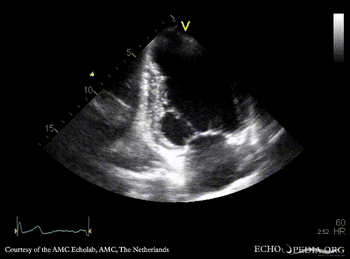

Apical aneurysm of LV

A4CH: dilated left ventricle, apical aneurysm A2CH: apical aneurysm